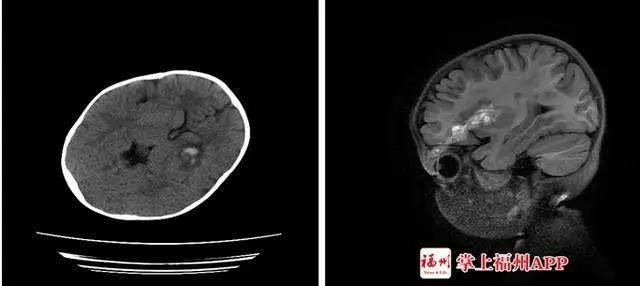

但是需要提醒的是,这款玩具具有危险性,家长购买时要慎重!不久,客厅传来嚎啕大哭声,小美妈妈闻讯赶来,只看到玩具上的不锈钢软轴已插入小美左眼上方。接诊专家介绍,软轴刺入造成了小美开放性颅脑损伤、颅内少量血肿、左眼眶上壁骨折伴左眼眶周围软组织挫裂伤。医生说:“万幸不锈钢软轴只是从眼球边上擦过,没造成眼球破裂。但还是出现了玻璃体积血,孩子后期视力可能会受影响。”而福建另一女童小文在独自玩这个文具时,支撑杆的接口突然断开,小文不慎往前跌倒,杆子从她的左眼刺进去,孩子血流不止,疼得大哭。家人赶紧把小文送到医院。医生发现,这根塑料杆有筷子般粗,插入了小文的左眼。CT检查显示,异物已进入颅内,导致颅内出血。全身麻醉后,神经外科医生帮小文拔出了杆子,观察一天后,她的状况稳定,才转院继续治疗。据了解,这种回弹软轴乒乓球结构简单,不用对手都可以自己一个人在家里打乒乓球。商家一再强调这款玩具安全性颇高,为了求证这一点,记者花35元买了一个同款玩具,哪知一开箱就暴露出了第一个安全隐患。